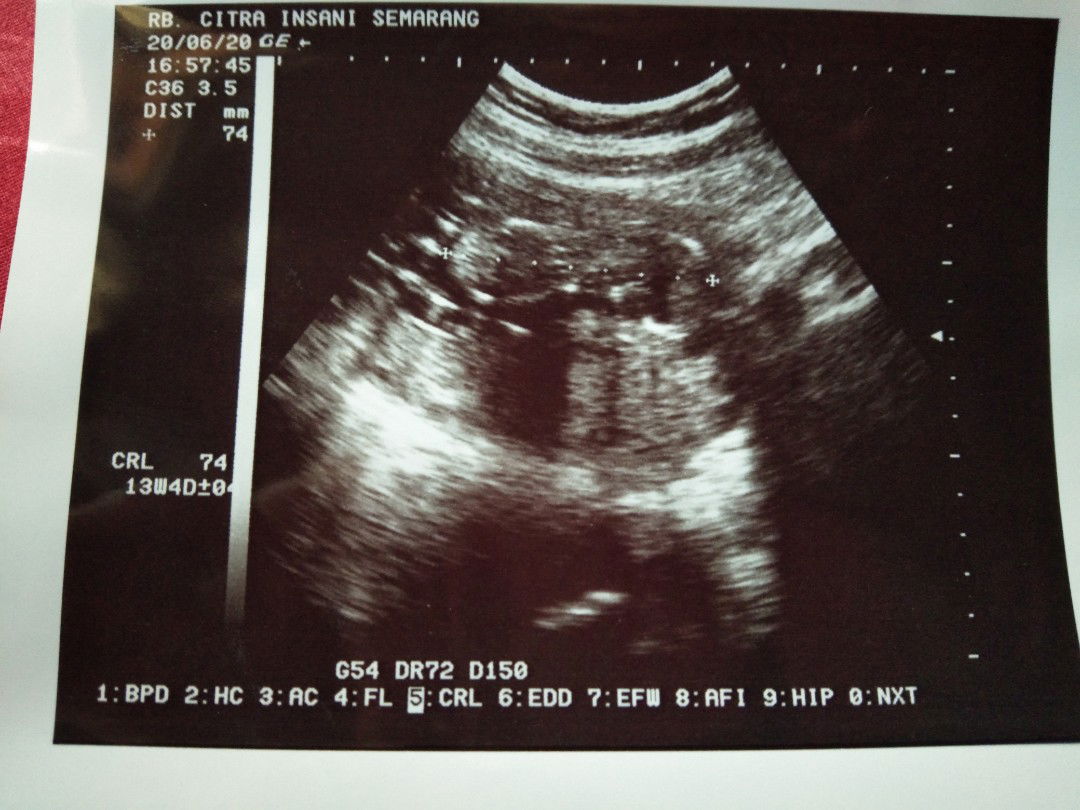

usg

Bun waktu usg posisi janinnya seperti itu apakah bahaya bun ? Saya jdi worry

Bun apa bener kalo setiap bulan periksa trus di usg itu ngga baik buat janin ?